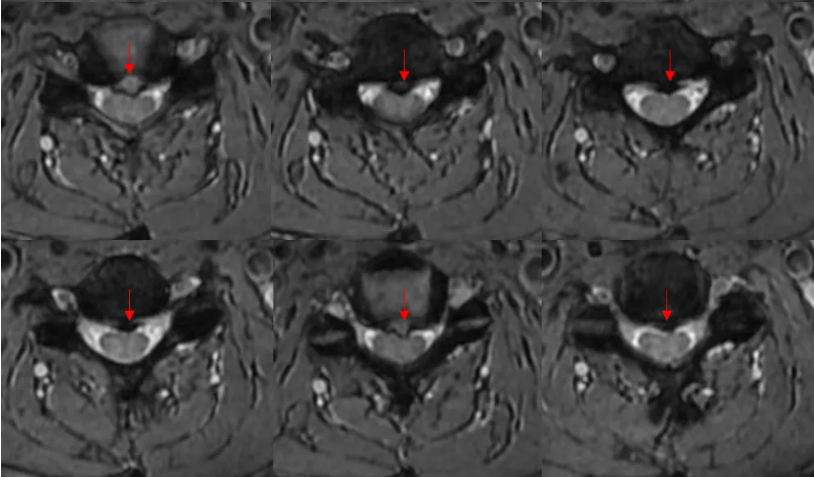

很简单。 椎间盘突出。 想看清椎间盘突出,最好用的序列莫过于横断面梯度回波序列T2*WI MERGE(multiecho recalled gradient echo,多回波的梯度回波序列)。与常规T2WI FSE序列相比,其优点在于脑脊液流空伪影很少。所以,脑脊液呈显著高信号,突出的椎间盘呈低信号,二者之间对比差异很大,图像效果杠杠滴。

小编以后也要注意脊柱大保健了(写到此处,小编无意识地活动了一下脖子)。 横断面T2*WI 梯度回波序列还有一个特点,脊髓的小蝴蝶显示比较好。 感觉这个患者小蝴蝶显示很一般啊。 这个垃圾机器。曾经有个教授的课件,小蝴蝶可漂亮了。。。 再翻一遍图像,好像脊髓怪怪的。

伪影吧。参数有问题。机器好久没有停机保养了。 放病人下来? 赶紧弄下一个, 晚饭约了心仪许久的妹子(帅哥)。。。 三、放患者走,还是继续扫描? 这是一个哲学问题! Ax CUBE T2FLAIR来一个吧。妹子(帅哥)应该不会因为晚到4分钟生气吧。。